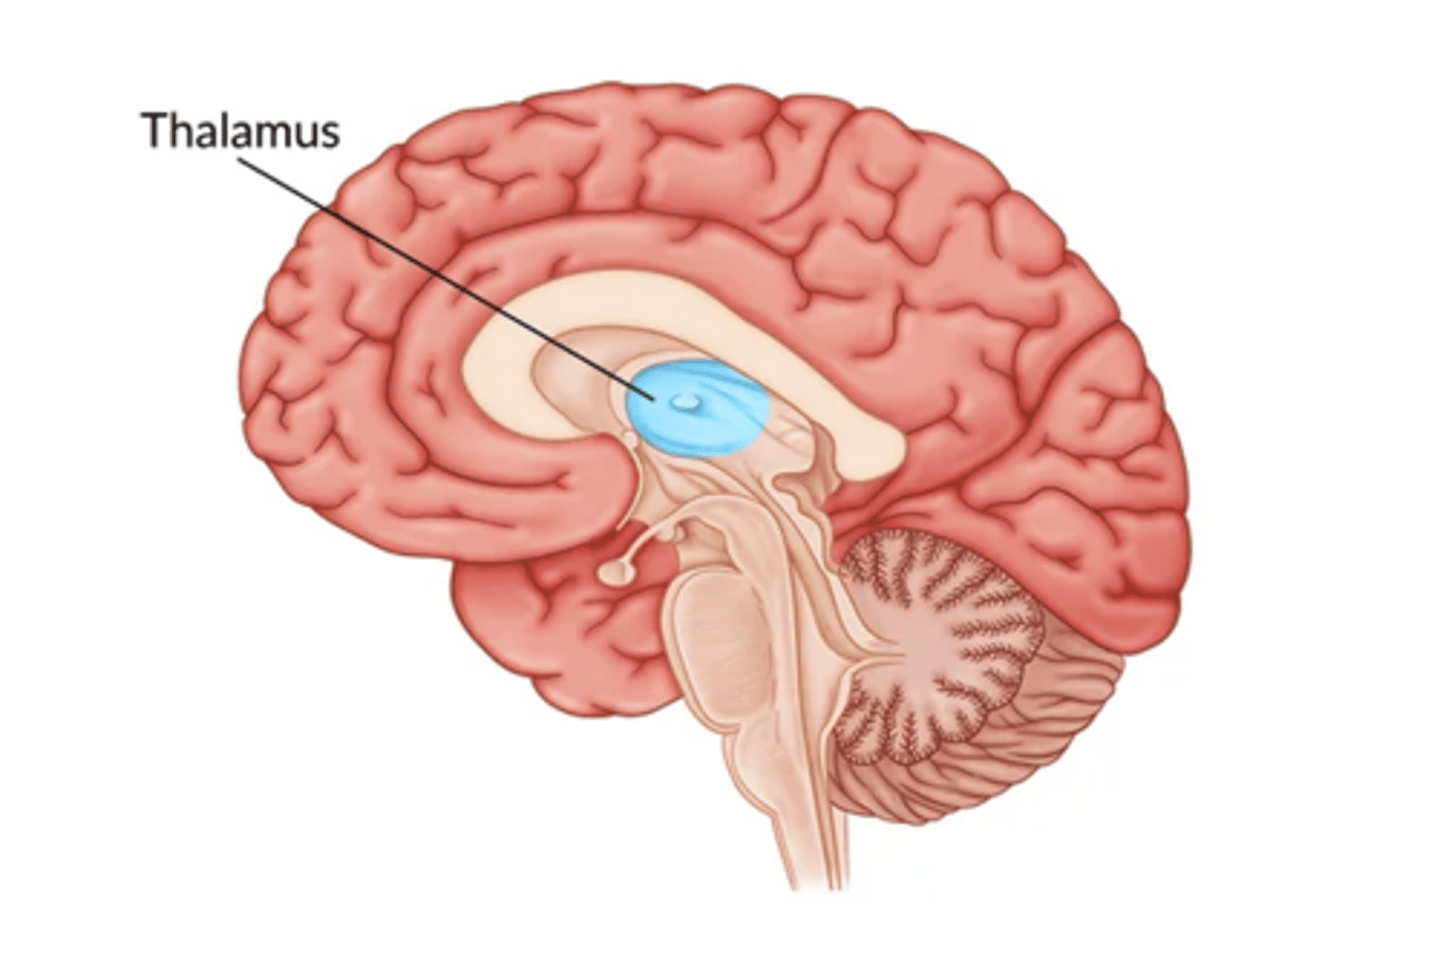

What is the function the thalamus?

sensory relay station

Where is the hypothalamus in relation to the thalamus?

anteroinferior (in front and below)

Where is the epithalamus in relation to the thalamus?

posterosuperior (behind and above)